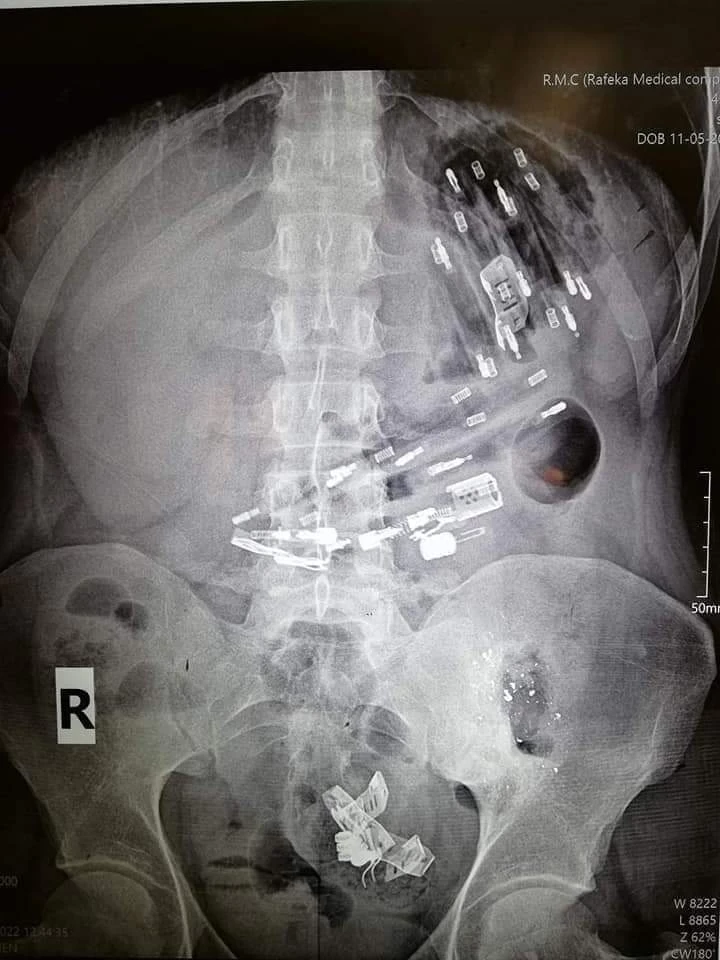

راجع مريض نفسي بحالة بطن حادة ...بعد التصوير تبين وجود أجسام أجنبية ضمن المعدة و الكولونات تم أجراء فتح بطن أسعافي وأستخراج مجموعة من القداحات و أجسام معدنية أخرة... كما هو مبين في الصور المرفقة....

- راجعنا اليوم مريض يبلغ من العمر ٢٨ عاماً بشكاية ألم في البطن، وبالتصوير الشعاعي تبيّن وجود عدد من الأجسام الغريبة موزعة في بطنه.

- أجريت عملية استخراج الأجسام الغريبة والبالغ عددها 25 جسماً، تنوعت بين الأسلاك والأجسام المعدنية، إضافة لـ ١٧ "قداحة"، ويخضع المريض حالياً للمراقبة الطبية.